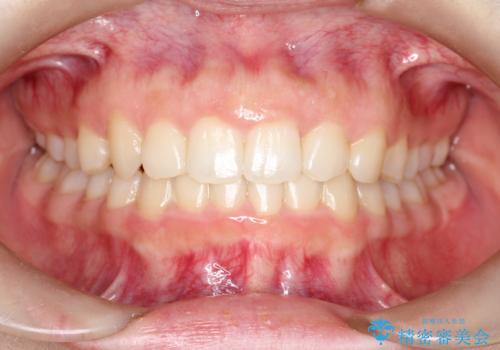

強い叢生がありましたが、抜歯は行わず上下顎ともに、主に歯列弓の拡大を行い叢生を改善しました。

見た目、嚙み合わせ及び、治療期間や施術内容に大変ご満足いただきました。